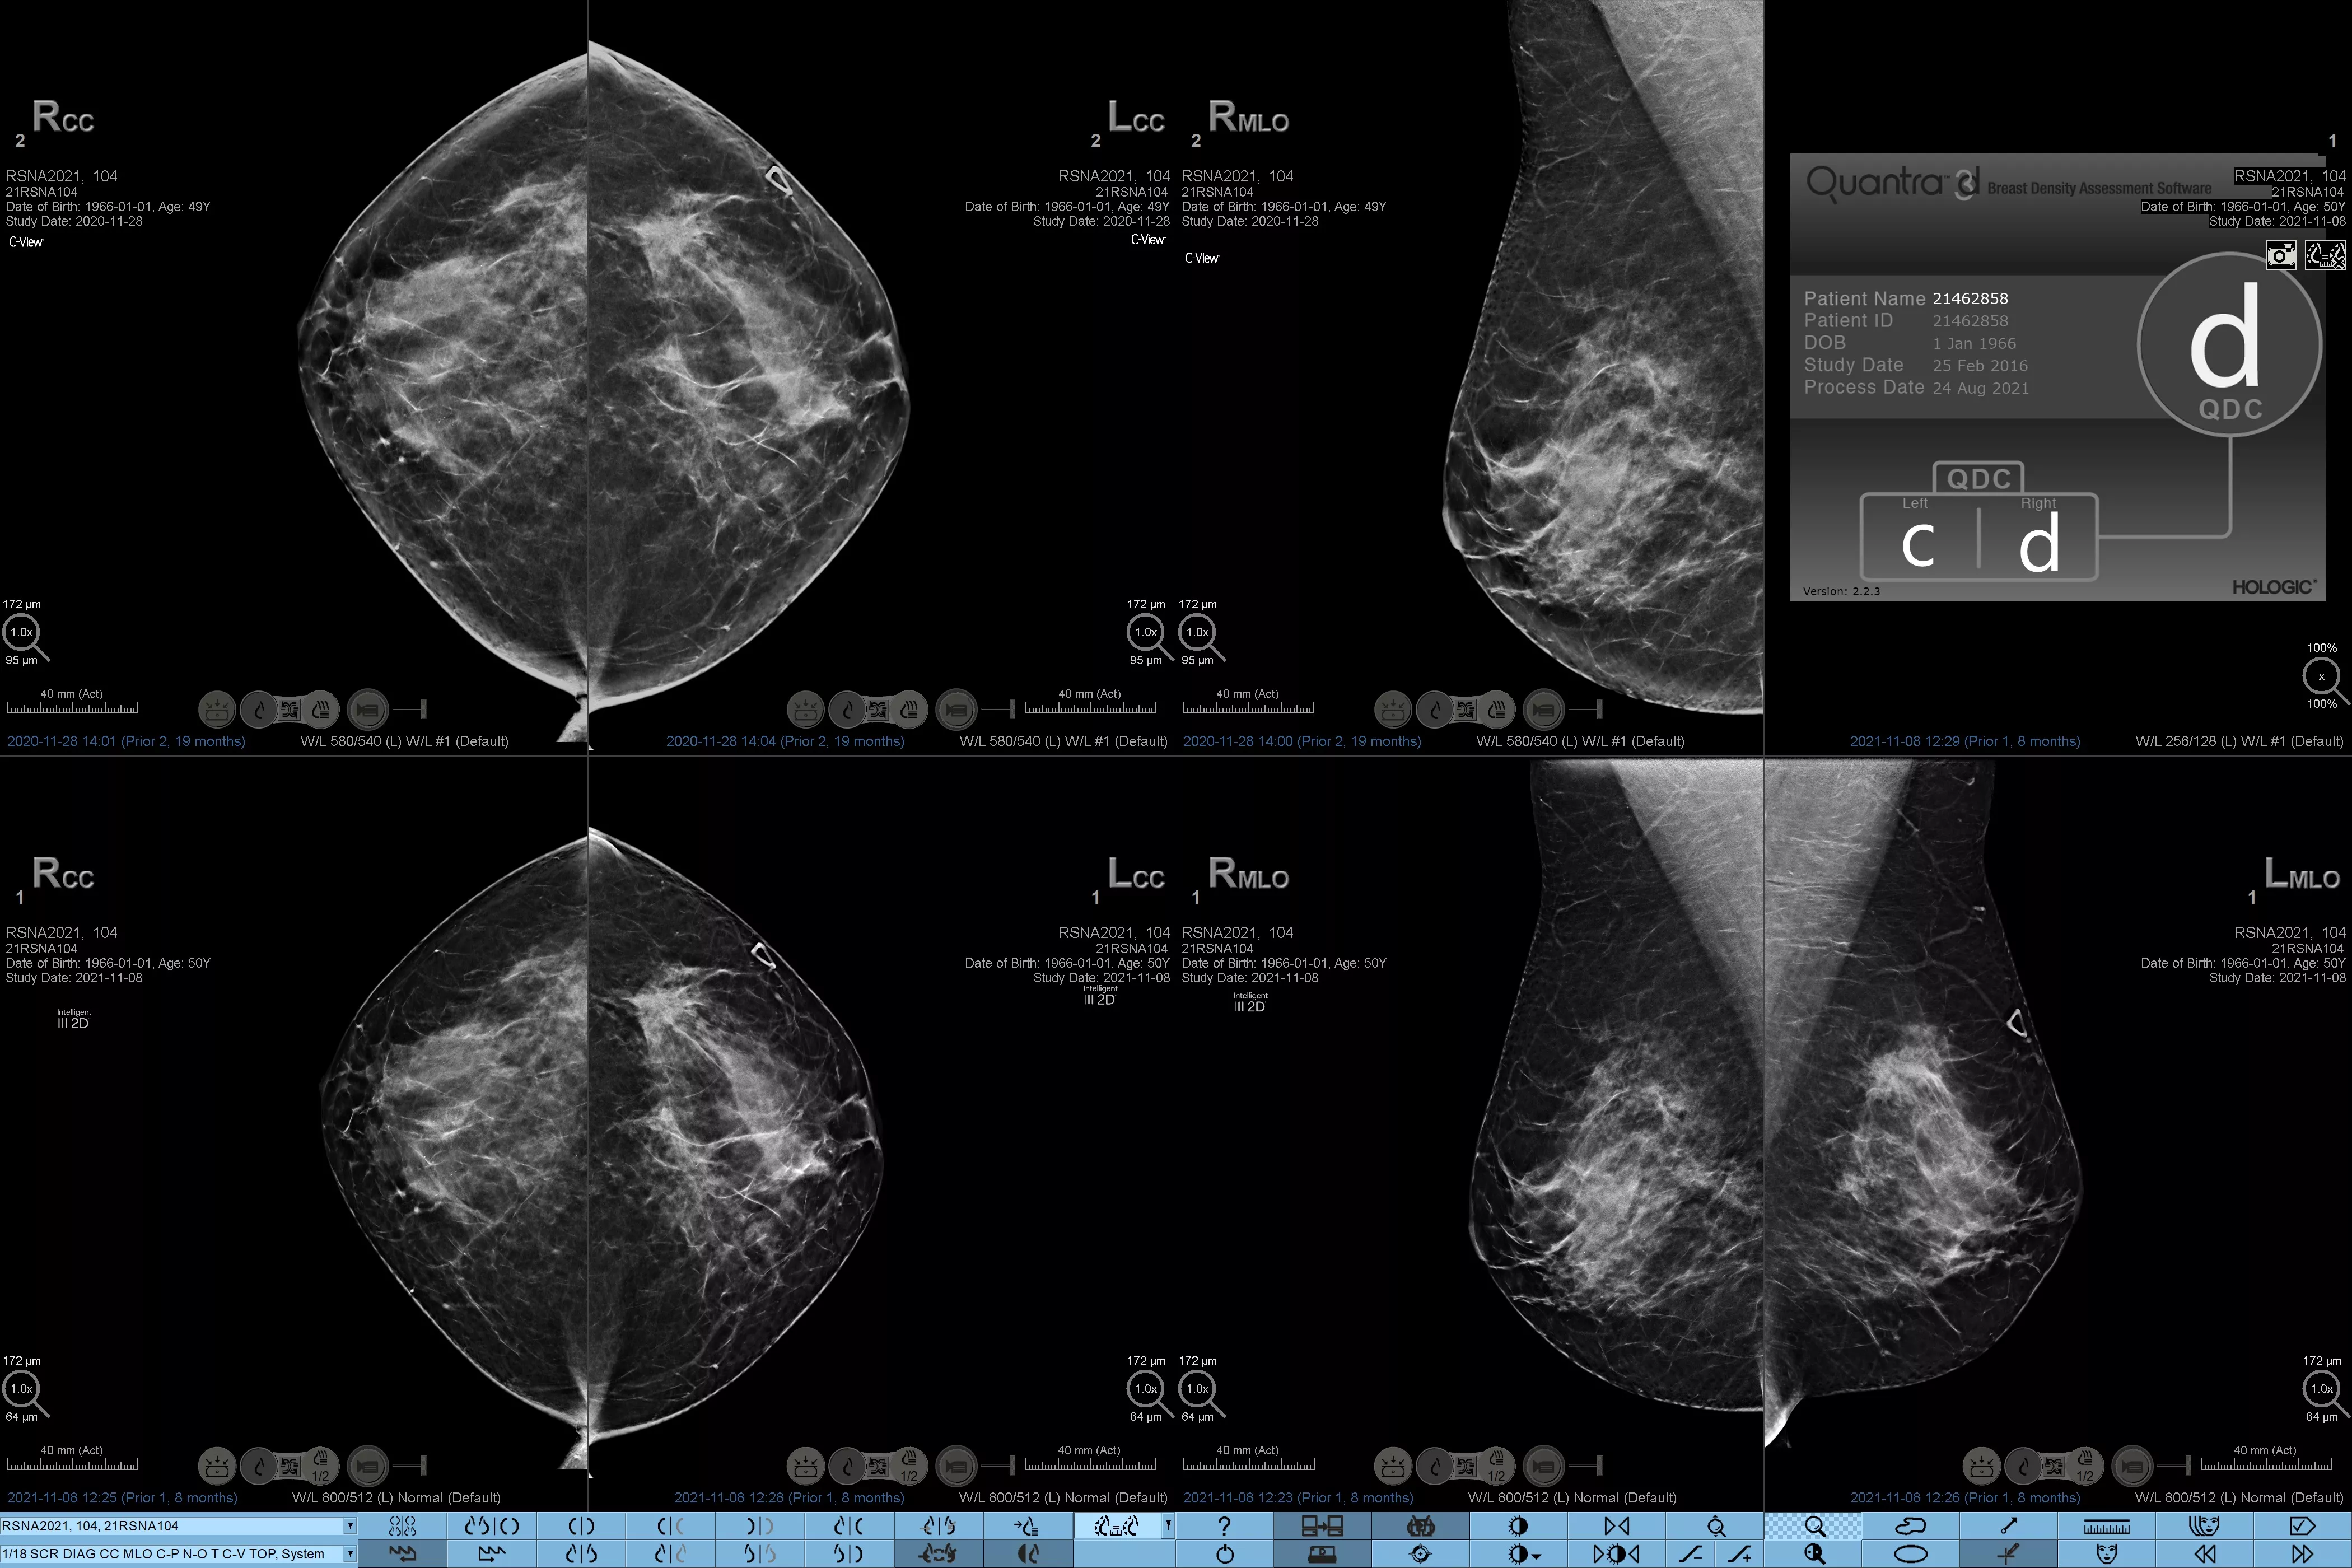

Higher breast density is known to increase a woman’s risk for breast cancer.1 The need for accurate, unbiased analysis is therefore critical. Powered by machine learning, Quantra technology software analyses both 2D™ and tomosynthesis images for distribution and texture of parenchymal tissue. It categorises breasts in four breast composition categories consistent with guidance from the American College of Radiology (ACR) BI-RADS Atlas 5th Edition.2

In addition to volume, pattern and texture of fibroglandular tissue may play just as an important role in mammographic cancer risk prediction.3-5 By analysing and categorising breast texture and pattern, our technology can deliver the accurate information you need to achieve more consistent and reliable scoring and confidently design patient-specific screening.

Objective machine learning algorithm that assigns breast density category based on analysis of breast tissue texture and patterns.

Quantra software’s unbiased algorithm analyse both 2D and tomosynthesis images to support your analysis by:

• Overcoming subjectivity in visual assessment, providing more consistent, and more reliable scoring.*

• Elevating the standard of care and standardises reporting.

*Scores are based on ACR BI-RADS categories, in line with the revised guidance by the American College of Radiation (ACR) BI-RADS Atlas 5th Edition. This accounts for pattern and texture, compared with volume, when determining density.